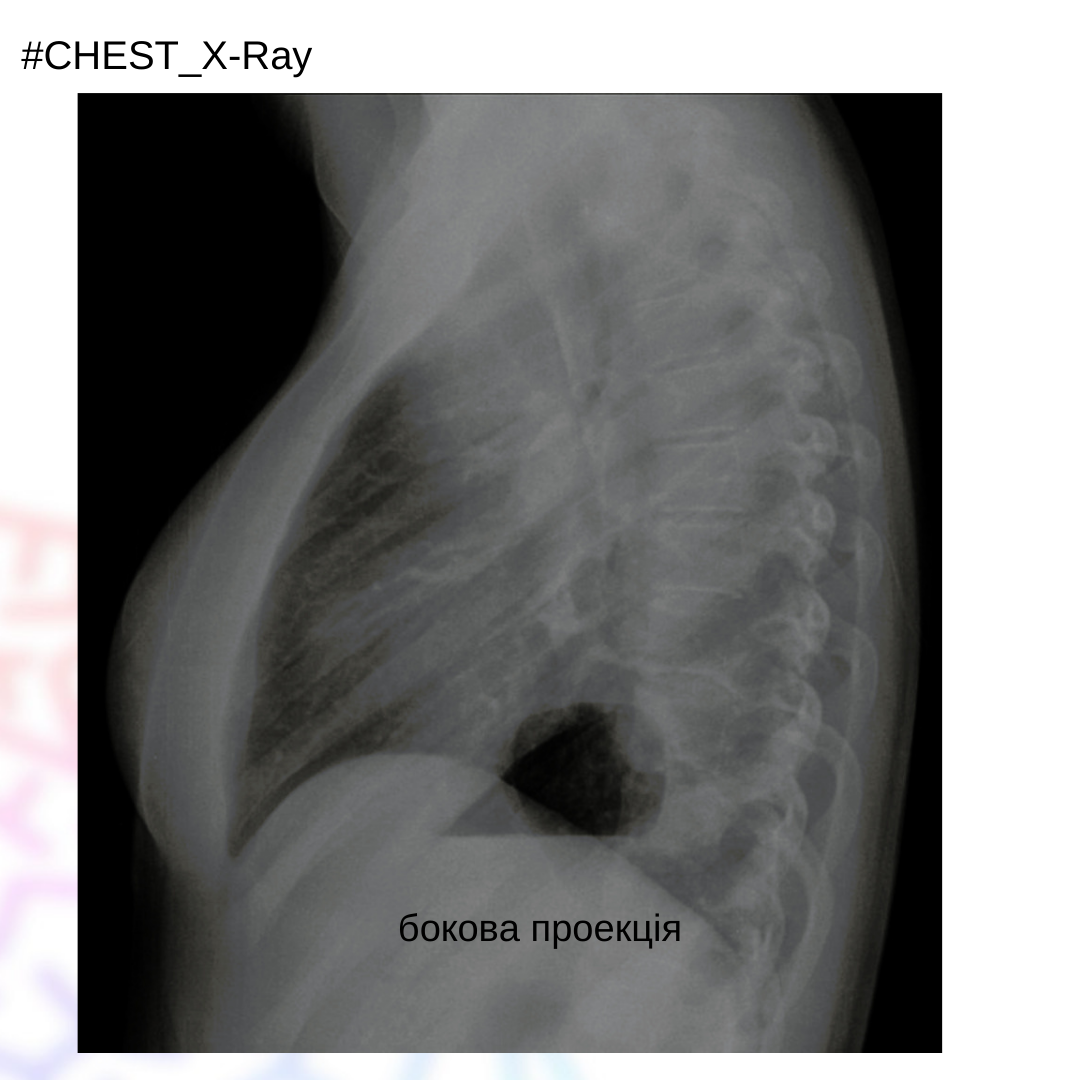

Жінка 30 років, зі скаргами на задишку та кашель протягом 4х тижнів.

На рентгенограмі ОГК спостерігається зменшенням об‘єму лівого гемітораксу зі зміщенням трахеї вліво та зміщенням ребер. Спостерігається затемнення лівої половини грудної клітки. Лівий купол діафрагми не візуалізується. Лівий головний бронх «обрубаний».